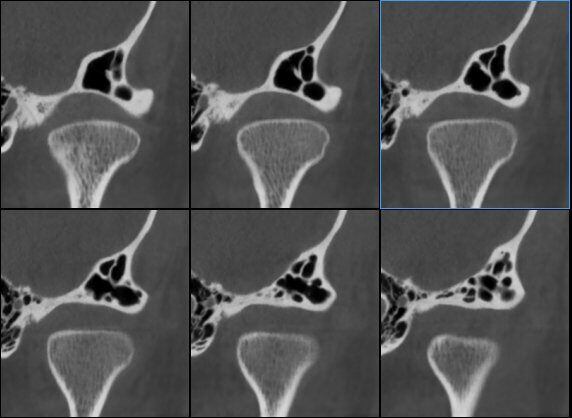

Catena Ossiculare e Nervo Facciale